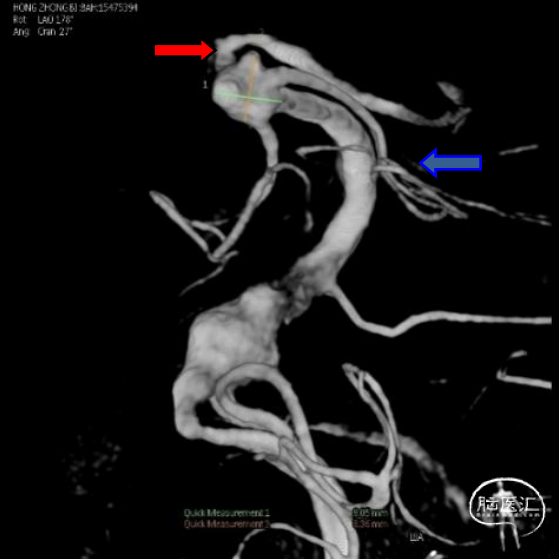

入院后立即行脑血管造影提示椎基底冗长扩张(基底动脉脑桥部分最宽处约5.2mm),伴有基底动脉多发动脉瘤,基底动脉尖动脉瘤(最大径约8mm)伴子囊和基底动脉下段动脉瘤(最大径约11mm)(图2)。

该患者在发病前并无症状,发表后为典型的动脉瘤性蛛网膜下腔出血的表现,剧烈头痛,CT平扫表现为广泛蛛网膜下腔出血和脑积水。CTA提示椎基底冗长扩张伴有动脉瘤。VBD患者伴有动脉瘤破裂常常分为两种,一种是囊状动脉瘤破裂,治疗方式与其他部位囊状破裂动脉瘤类似;另一种是梭形动脉瘤,大的梭形动脉瘤处理相对困难。有文献报道多个编织支架重叠的方法能够改善患者预后[8]。对于出现脑干压迫症状的患者血管内治疗效果欠佳,近一半的患者死亡[9]。此患者有两个动脉瘤,基底动脉尖动脉瘤更接近囊状动脉瘤,而基底动脉下段动脉瘤为大型梭形动脉瘤。对于基底动脉尖动脉瘤我们采取常规的动脉瘤栓塞策略,弹簧圈填塞集中在动脉瘤囊内,尤其是动脉瘤子囊的填塞。对于基底动脉下段动脉瘤我们采取大尺寸弹簧圈在梭形动脉瘤内均匀分布,使用大尺寸的LVIS支架尽可能使其与基底动脉能够较好贴壁从而能够促进血管壁的重建。对于弹簧圈结合支架治疗的方法有脑干穿支血管闭塞风险。近期有学者使用高分辨CTA对VBD患者进行分析,发现基底动脉扩张明显处的脑干穿支血管消失,而由其上、下方的血管通过软膜血管吻合提供代偿性血流[10]。因此在基底动脉明显扩张甚至形成梭形动脉瘤处使用弹簧圈疏松填塞是相对安全的,从此患者术后的神经功能以及CT和DWI结果得到了验证。此外进一步闭塞一侧椎动脉促使动脉瘤内血栓形成提高血管壁重建的可能[11]。